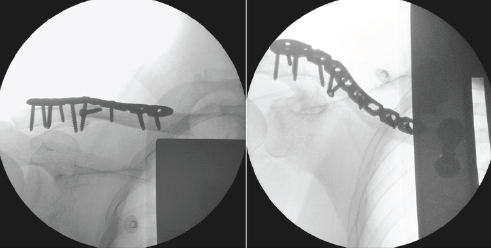

Further dissection was employed to retrieve the inferior fragment with the coracoid ligament attached. The reduction lag screw technique was employed to aid in the reduction of the inferior fragment. A 3.5 mm drill was used for the gliding hole created at the cortical screw hole of the plate – overlying the inferior fragment. A pilot hole was drilled through the inferior fragment using a 2.5 mm drill. An initial 3.5 mm cortical screw was applied to engage the inferior fragment (pilot hole). As the lag-screw was advanced, the inferior fragment was reduced toward the main clavicle fragments (Fig. 3). The reduction of the inferior fragment was then reinforced by tying cerclage braided sutures around the main clavicle fragment.

Figure 3: Reduction of the inferior fracture fragment using the lag screw technique.